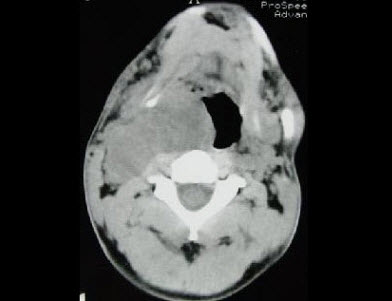

男,41岁,右侧咽部不适两年余,有异物感,声音嘶哑,CT如图所示,最可能诊断为()。

A、颈动脉体瘤

B、咽旁转移癌

C、咽旁淋巴瘤

D、小唾液腺瘤

E、咽旁神经鞘膜瘤

E